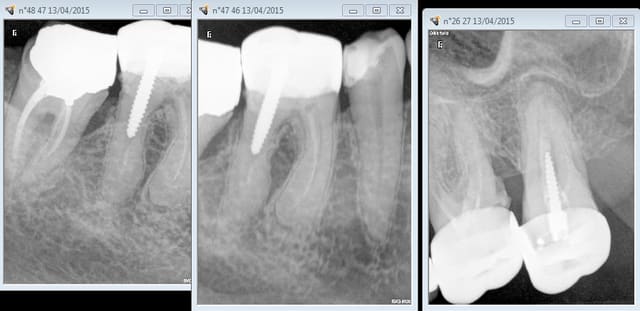

Je vous fais passer la radio qui montre une image au niveau du septum 35 36 et je suis vraiment étonné qu'en l'espace de si peu de temps je puisse avoir une telle lésion.

Merci pour vos avis,en grossissant la radio on peut effectivement penser à une fracture de la racine.Ce n'est pourtant pas la racine qui supporte le tenon.